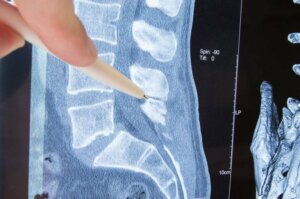

Rygsøjlen eller rygraden er en knoglestruktur dannet af ryghvirvler, som beskytter knoglerne, og gør det muligt at bevæge sig frit. Ryghvirvlerne har hul i hver side, hvorfra der udgår nerver til forskellige dele af kroppen.

Den del af nerven der kommer ud af ryghvirvlerne, kaldes nerverødder. Radikulopati er sammenpresning af nerven, netop ved nerveroden. Hvad forårsager det? Hvordan manifesterer det sig klinisk? I denne artikel svarer vi på de spørgsmål, og informerer dig om de eksisterende behandslingsmuligheder.